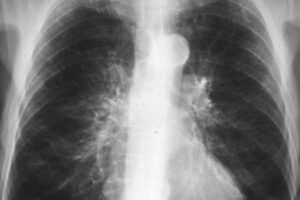

Причины и лечение нейроэндокринной карциномы (мелкоклеточного рака) легких

Нейроэндокринный рак легкого (NERLC, NELC) относится к сложной и чрезвычайно разнородной категории злокачественных новообразований эпителия, в том числе рака различной степени дифференцировки. В эту группу онкологических заболеваний входят типичные и атипичные карциноиды, а также крупноклеточные и мелкоклеточные опухоли. Общая информация Нейроэндокринные новообразования легких и бронхов составляют 27% всех вариантов SEO, занимая второе место по частоте …